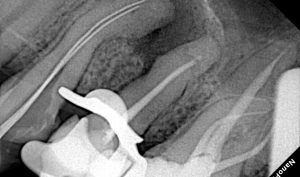

• лікування кореневих каналів зубів